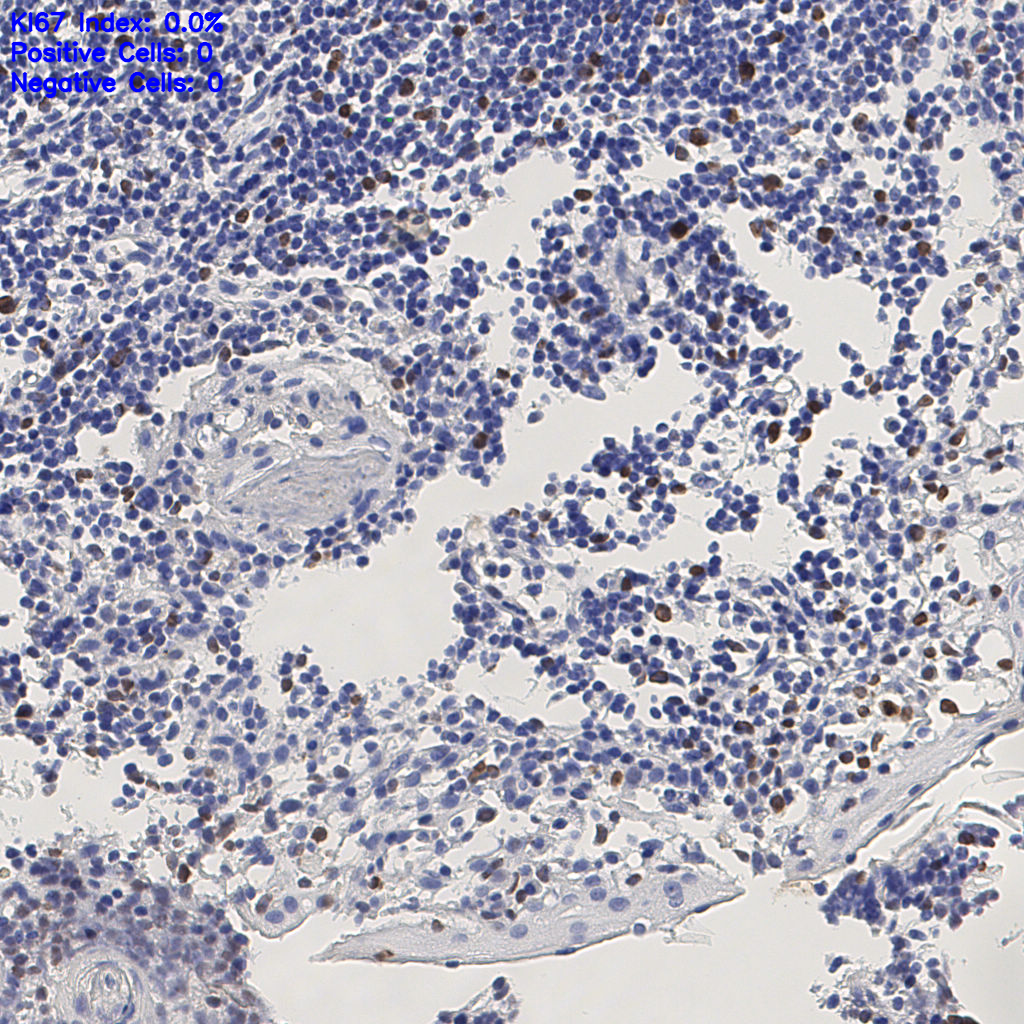

7.85%

Ki67 指数

阴 1104

阳 94

切片统计

有效

288